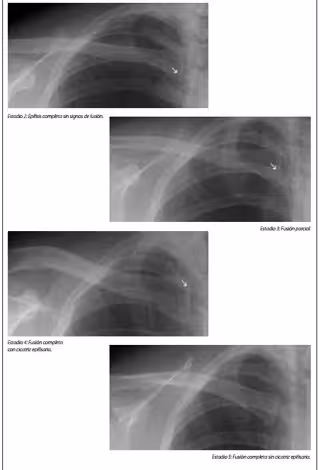

Según explica Fundación Raíces, el protocolo avala así el proceder de la Fiscalía, que sistemáticamente somete a los menores extranjeros a estas pruebas médicas que van de una radiografía de muñeca a una exploración de dentición y genitales y que arrojan una horquilla de resultados por las que un menor puede ser tomado por adulto, perdiendo así la tutela pública y la protección que esta conlleva.